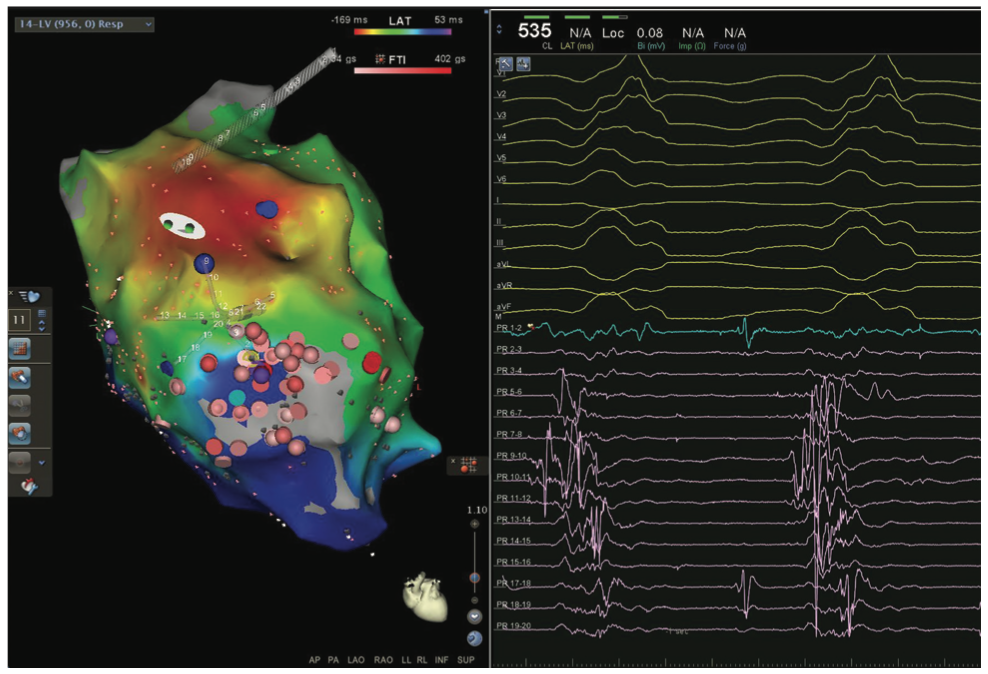

Videos 13a-b and Figure 13c demomstrate a zero fluoroscopic ischemic, incessant, hemodynamically tolerated VT ablation and creation of a 4-chamber EAM/sound map and a figure-of-8 VT in a patient with a large anteroapical infarction along with the electrogram resolution afforded by small 1-mm electrodes of the Pentaray in the isthmus corridor.